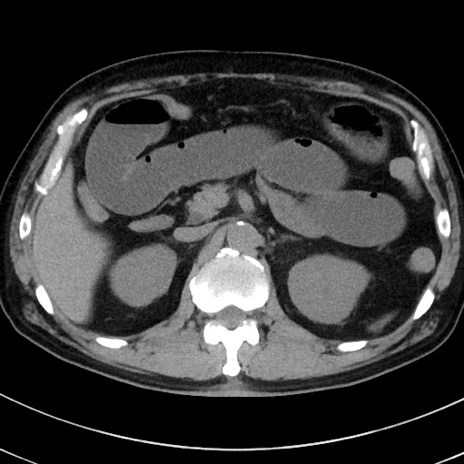

症例38(横断像)

【症例】70歳代 男性

【主訴】腹痛・嘔吐

【現病歴】昨晩より、嘔吐・腹痛あり。今朝になっても嘔吐あり。来院。

【既往歴】心臓バイパス手術、開腹胆摘、腸閉塞

【身体所見】BP 107/71mmHg、HR 116/min、腹部:平坦、軟、下腹部に軽度圧痛あり。反跳痛なし。

【データ】WBC 15100、CRP 0.32